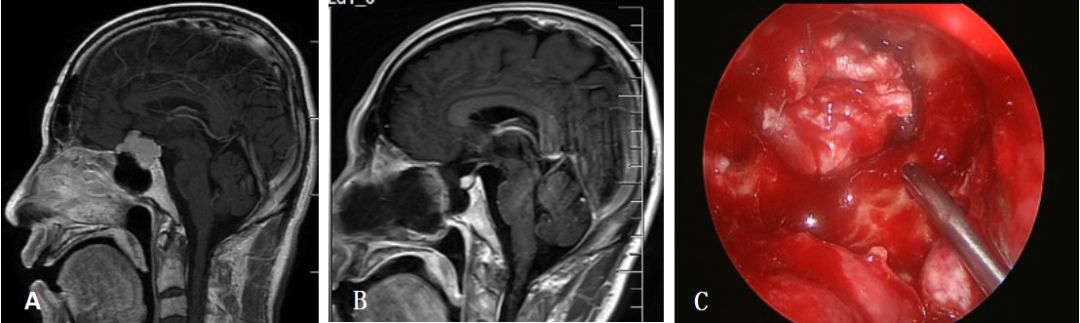

病例1:颅咽管瘤

图3. A:颅咽管瘤术前矢状位MRI;B: 颅咽管瘤术后矢状位MRI;C:自体阔筋膜连续缝合修补颅底硬膜。